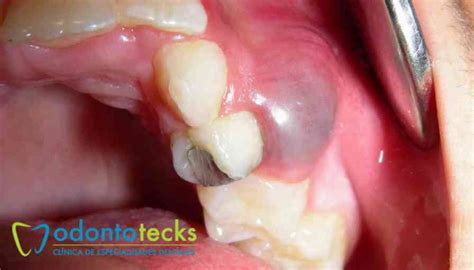

Si de repente detectas que tu encía se inflama en determinada zona, y que comienza a formarse una pequeña fístula por encima del diente, podemos estar hablando de un quiste dental u odontogénico. Este se caracteriza además por ser semiblando y escamoso al tacto.

Es una lesión en forma de bulto, ubicada generalmente en el interior de los huesos maxilares de la boca. Esta lesión o cavidad se llena de líquido o material semi-sólido, caracterizándose por ser semiblando y escamoso al tacto. Los quistes dentales son en su mayoría, benignos, es decir, no son cancerosos.

La encía comienza a presentar dolor e inflamación localizada y pueden aparecer llagas en la zona. Se produce una reabsorción de las raíces próximas al quiste dental. Puede aparecer una protuberancia semiblanda en la encía cuyo interior está formado por pus. Es común, también, sufrir de sensibilidad en los labios.